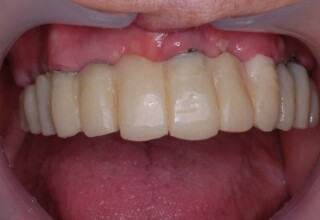

Lower jaw: extractions, direct implant placement and immediate loading (same day) with a transitional bridge.

Upper jaw: Sequential extractions, sequential implant placement and gradual incorporation in the temporary bridge so that the patient was never left without fixed teeth. The aim of the above approach was to have the patient in continuous functional and aesthetic reconstruction, without immediate loading due to anatomical restrictions. Old smiling photos of the patient were used because the natural shape of the teeth was completely lost due to repetitive prosthetic attempts. Tooth relationship and teeth-lip support was transferred to the temporary restorations. Two different transitional bridges were needed to fully estimate phonetics, mastication and esthetics. After the necessary adjustments were finalized, the temporary bridge was used as a guide for the permanent bridges.

Final